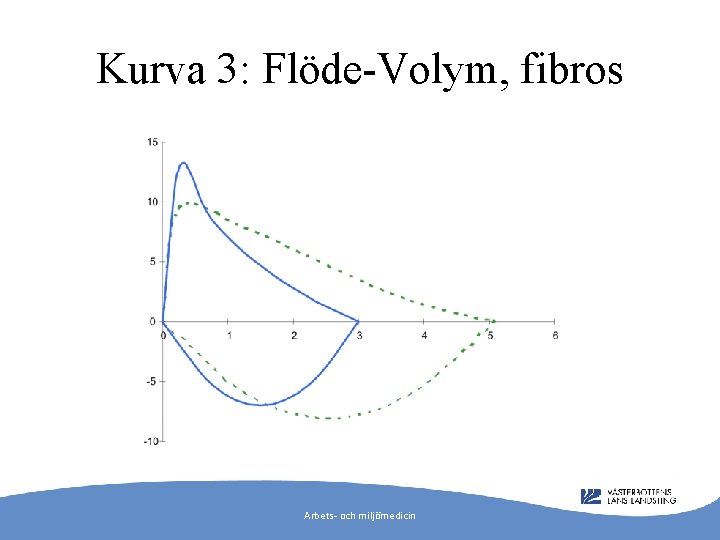

Kurva 3: Flöde-Volym, fibros Arbets- och miljömedicin